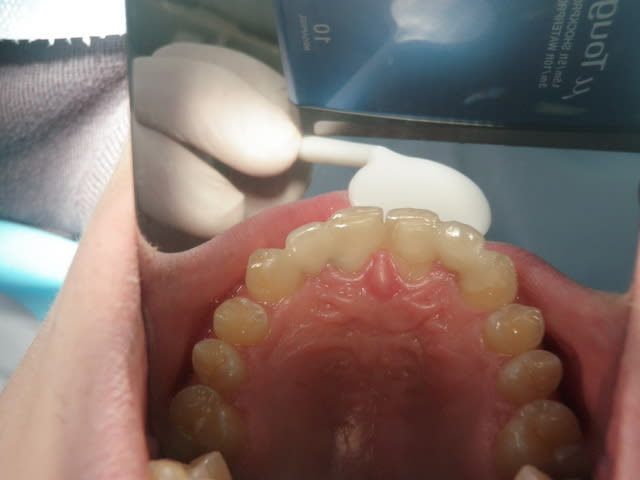

26/11/2010 à 22h47

préparations pour bridge collé ...des commentaires?

> préparations pour bridge collé ...des commentaires?

oui, les photo sont floues

Sérieusement, j'aimerais mieux voir et voir aussi l'oclusion.

Si non, ça me semble bien

tu fais un léger retour vestibulaire en mésial des canines, tu ne crains pas que ça devienne visible?

sinon occlusion? et ça parait bien.

pas vraiment de retour mais je souhaitais modifier légèrement l'aspect morpho des canines,

l'occlusion était un peu serrée au niveau des centrales ,mais il y a agénésie des 41 et 31 et j'ai remodelé le bridge collée antagoniste provisoire.

La 13 semble avoir une limite trop vestibulaire en effet...faudra voir le collage final...